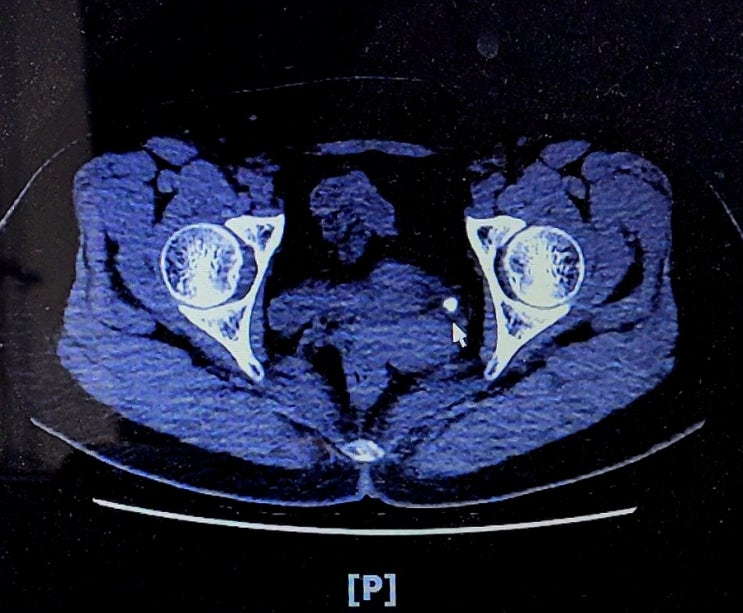

저절로 사라진 요로결석, 이젠 안녕? 부디부디~~

쇄석 했다고 했나요? "아니요! 아무것도 안했어요. 2월까지 계속 아팠어요." "음..꽤 크긴 ...